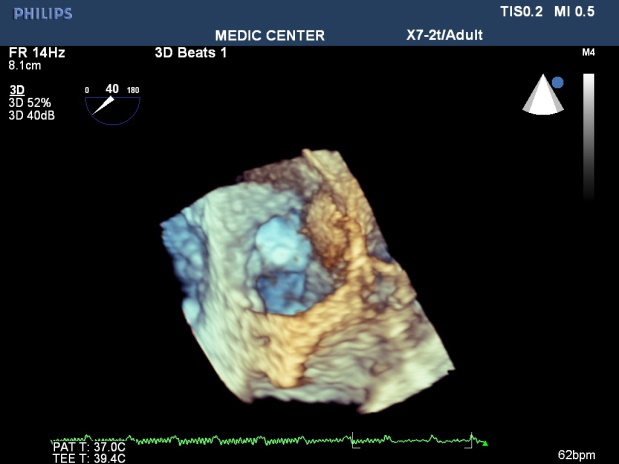

Some patients with high Wilkins score evaluated by 2DTEE still have responded well to Balloon Mitral Valvuloplasty. Real-time three-dimensional transesophageal echocardiography provides important informations regarding the involvement of rheumatic process on the mitral valve, particularly the symmetry length of commissural fusion. Furthemore RT-3DTEE also shows the thickening, the fibrosis and the calcification of the whole mitral commissures that cannot be visualized by 2DTEE. The 3D image allows superior visualization of the thickening of the mitral leaflet, particularly the commissures.

The 3DTEE usually details the subvalvular apparatus not appreciated on 2DTEE while studying the leaflets.

Direct planimetry of mitral valve orifice by 3DTEE is the gold standard method now. The cropping function ensures that the orifice area is traced in a plan that is at the tip of the mitral valve (Figures 2-17).

Figure 13. RT-3DTEE shows small and restrited mitral orifice, commissural  fusion, extensive rheumatic  nodules, severe deformity of mitral leaflets

Figure 14. Zoom 3DTEE image  visualizing the thickenned leaflets, commissural fusion,  nodules of rheumatic fever

Figure 16. Zoom 3DTEE  showing MS with comissural fusion and rheumatic nodules

Figure 17. Parasternal 3D TTE demonstrating fusion of commissures and rheumatic nodules

The cropping function on 3D TEE ensures that the orifice area is measured in a plane that is at the tip of the mitral valve and perpendicular to the inflow through the valve [12].